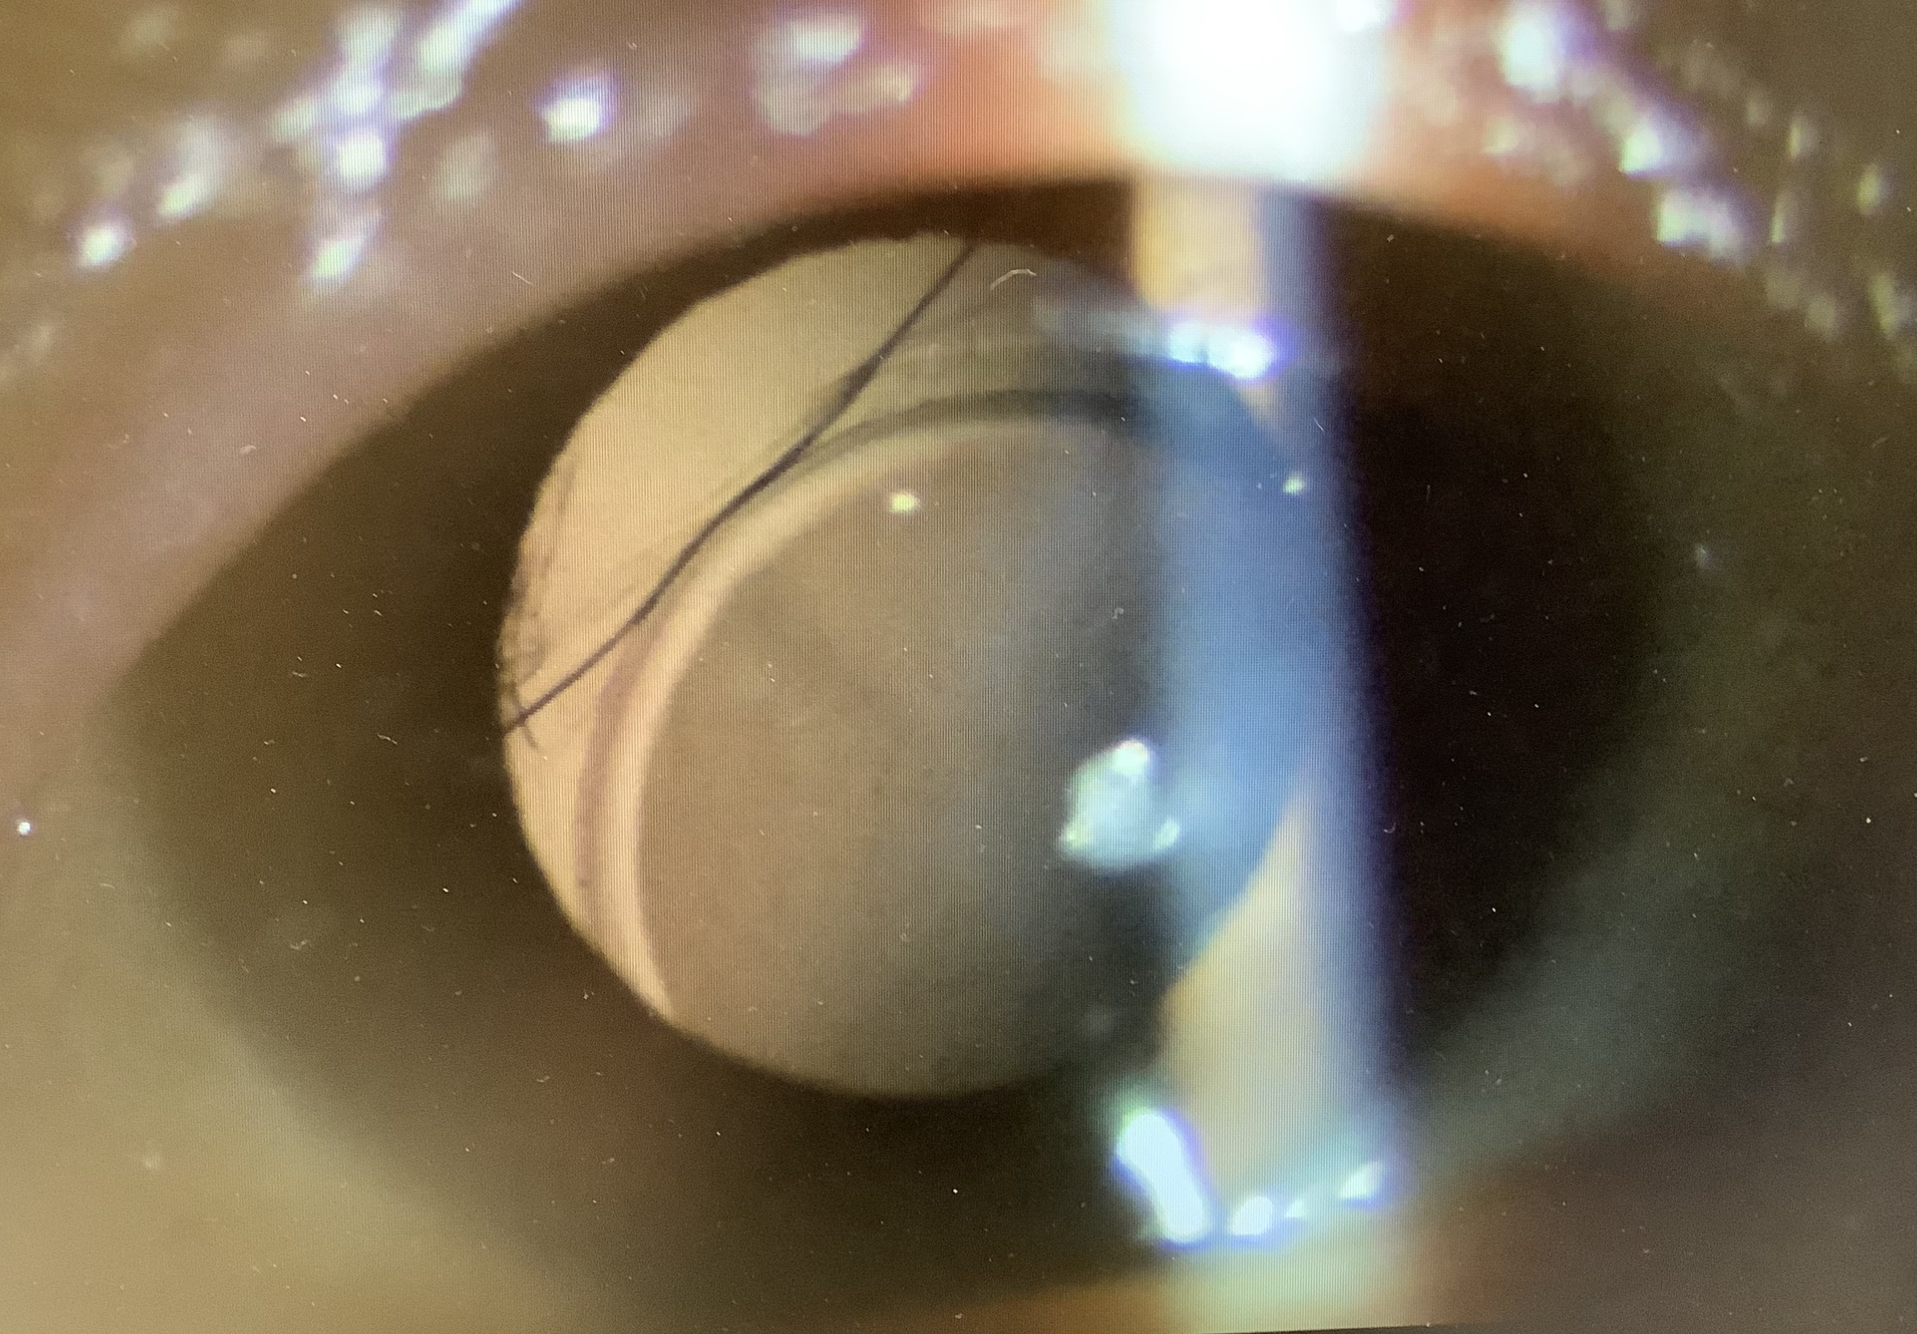

今日の手術は、有水晶体眼内レンズ(ICL)1人、白内障10件、翼状片切除1件、黄斑上膜の硝子体手術1件、眼内レンズ交換1件でした。

今日、眼内レンズ偏位で強膜内固定の手術の申し込みになった歳の男性は、レンティス・コンフォートが使われていましたが、レンティスのような単純な単焦点でないレンズが傾きズレると、その程度の割に視力下がり、自覚的にも嫌な見え方になってしまいます。今入っているレンズを取り出し、新たな眼内レンズを眼の壁に固定する強膜内固定が必要な旨をお伝えしたところ、『多焦点レンズを入れることはできますか?』という質問を受けました。その答えはなかなか難しく、『多焦点レンズは使えず、単焦点レンズを使うことになります』と答えましたが、正確には『多焦点レンズの強膜内固定もできなくはないが、基本的には単焦点レンズにすべきです』ということになります。強膜内固定には、支えの部分がレンズの本体と別に細い素材でできている“3ピース型の眼内レンズ”を使う必要があります。現在、主に使われている多焦点レンズは、1ピース型がほとんどですが、AMO社のZMAという多焦点レンズは1ピース型で強膜内固定に使うことができ、理論上は多焦点レンズを使った強膜内固定もできることになります。ただ、これで良好な遠近の見え方ができるかというと、そう単純な話ではありません。多焦点レンズは、眼の中心に偏りや傾きなく、きれいに収まっていることで、良好な見え方を実現できますが、強膜内固定では、レンズの支えを2点で眼に固定するため、その位置により、中心のズレやレンズの前後方向の傾きがどうしても多少は出てしまいます。単焦点レンズでは、軽度の偏心や傾斜があっても、見え方にそれほど影響しませんが、多焦点レンズでは大きな影響が出てしまう可能性が高くなってしまいます。そのため、強膜内固定で多焦点レンズを入れることは一応は可能ですが、十分な視機能を得られる保証はなく、むしろ見えにくさが出てしまうリスクもあり、できれば単焦点レンズを使った強膜内固定を行うべきです。ただ、そのリスクは承知でダメなら単焦点で強膜内固定をやり直す覚悟があり、どうしても多焦点レンズで強膜内固定を行いたいというなら、一応、理論上はできなくはないので、考えてもよいかもしれません(でも、おすすめはしません、、、)。